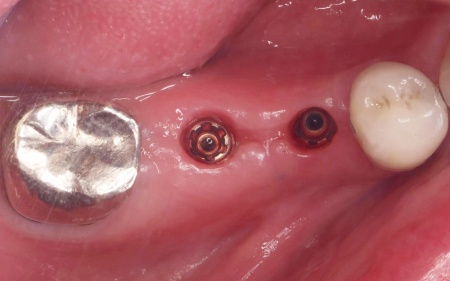

| 行ったご提案・治療内容 | 診断結果を丁寧に説明したうえで、右下奥歯2本の抜歯を提案したところ同意いただきました。 併せて抜歯後に歯を補う方法として、以下2つの選択肢をお伝えしました。 ①前後の歯を削って橋のようにつなげた被せ物で歯を補うブリッジ治療 ②あごの骨に人工の歯根を埋め込み、その上に人工歯を取り付けるインプラント治療 それぞれの特徴や注意点について説明したところ、患者様は②のインプラント治療を希望されました。 まず右下奥歯2本の抜歯を行い、その後、約3ヶ月間歯ぐきや骨が十分に回復するのを待ちました。 |

治療中